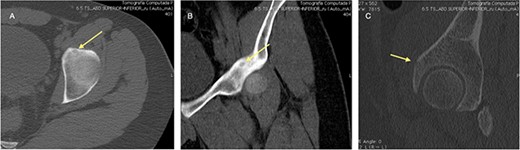

An 18-year-old male with 18 months of left hip pain was referred to an orthopedic surgeon for evaluation. Pain occurred with all hip movements, predominantly at night. Physical examination of the hip showed pain with deep palpation on the groin and positive test for flexion adduction and internal rotation and Patrick test. X-rays were obtained and femoroacetabular impingement (FAI) with labral tear was suspected (Fig. 1). A magnetic resonance imaging (MRI) showed no hip labrum or chondral defect. Measurements for bone deformities of cam and pincer were normal. Physical therapy and nonsteroidal anti-inflammatory drugs were prescribed with some pain relief especially at night. After no improvement of symptoms he was evaluated by a hip surgeon. Intra-articular hip injection with steroids was given and pain disappeared but nocturnal pain recurred after 24 h. Due to the clinical setting and poor response to pain management, an OO was suspected and (CT) was ordered where a 6 mm sclerotic bone tumor with a nidus in the anterior rim of the left acetabulum was identified and corresponded with the pain localization (Fig. 2).

CT scan of the left hip showing a 6-mm extra-articular OO on the anterior rim of the acetabulum (yellow arrow).

The OO was <10 mm and was near the neurovascular structures so percutaneous CT guided curettage was considered the best option.

The procedure was made with general anesthesia and in supine position. A 1-cm incision was made for an anterior approach over the hip joint. Careful blunt dissection was done. Percutaneous technique was used with the guidance of a 64 slice Somatom sensation CT scanner (Siemens AG Munich, Germany) with interval cuts of 2 mm to locate the OO. Intravenous contrast was administered to identify the vascular structures at risk (Fig. 3). A 13G × 100 mm bone marrow biopsy needle was used. Image guidance was performed by a senior radiologist (ES). Once the OO was located, accurate insertion of the needle was monitored, and drilling was done manually to help precision in depth (Fig. 4). Multiple bone fragments were obtained and sampled. Immediate image verification showed a space missing the nidus OO. To avoid leaving remnant nidus, curettage was added on the edges and the deep margin of the tumor. Bone samples were sent to histological evaluation and OO diagnosis was confirmed. Wound pain management was administered for 2 weeks and night symptoms disappeared immediately. Complete relief was achieved 3 weeks later. A 12-month follow-up post treatment reported no recurrence of pain and no complications with wound management. ROM and athletic activities are painless. No soft tissue complications were reported.

CT with intravenous contrast showing the femoral vessel (yellow arrow) before the procedure to obtain proper approach (red arrow showing the OO).

CT showing the precise site for needle insertion (A), CT control of the needle insertion (B,C).